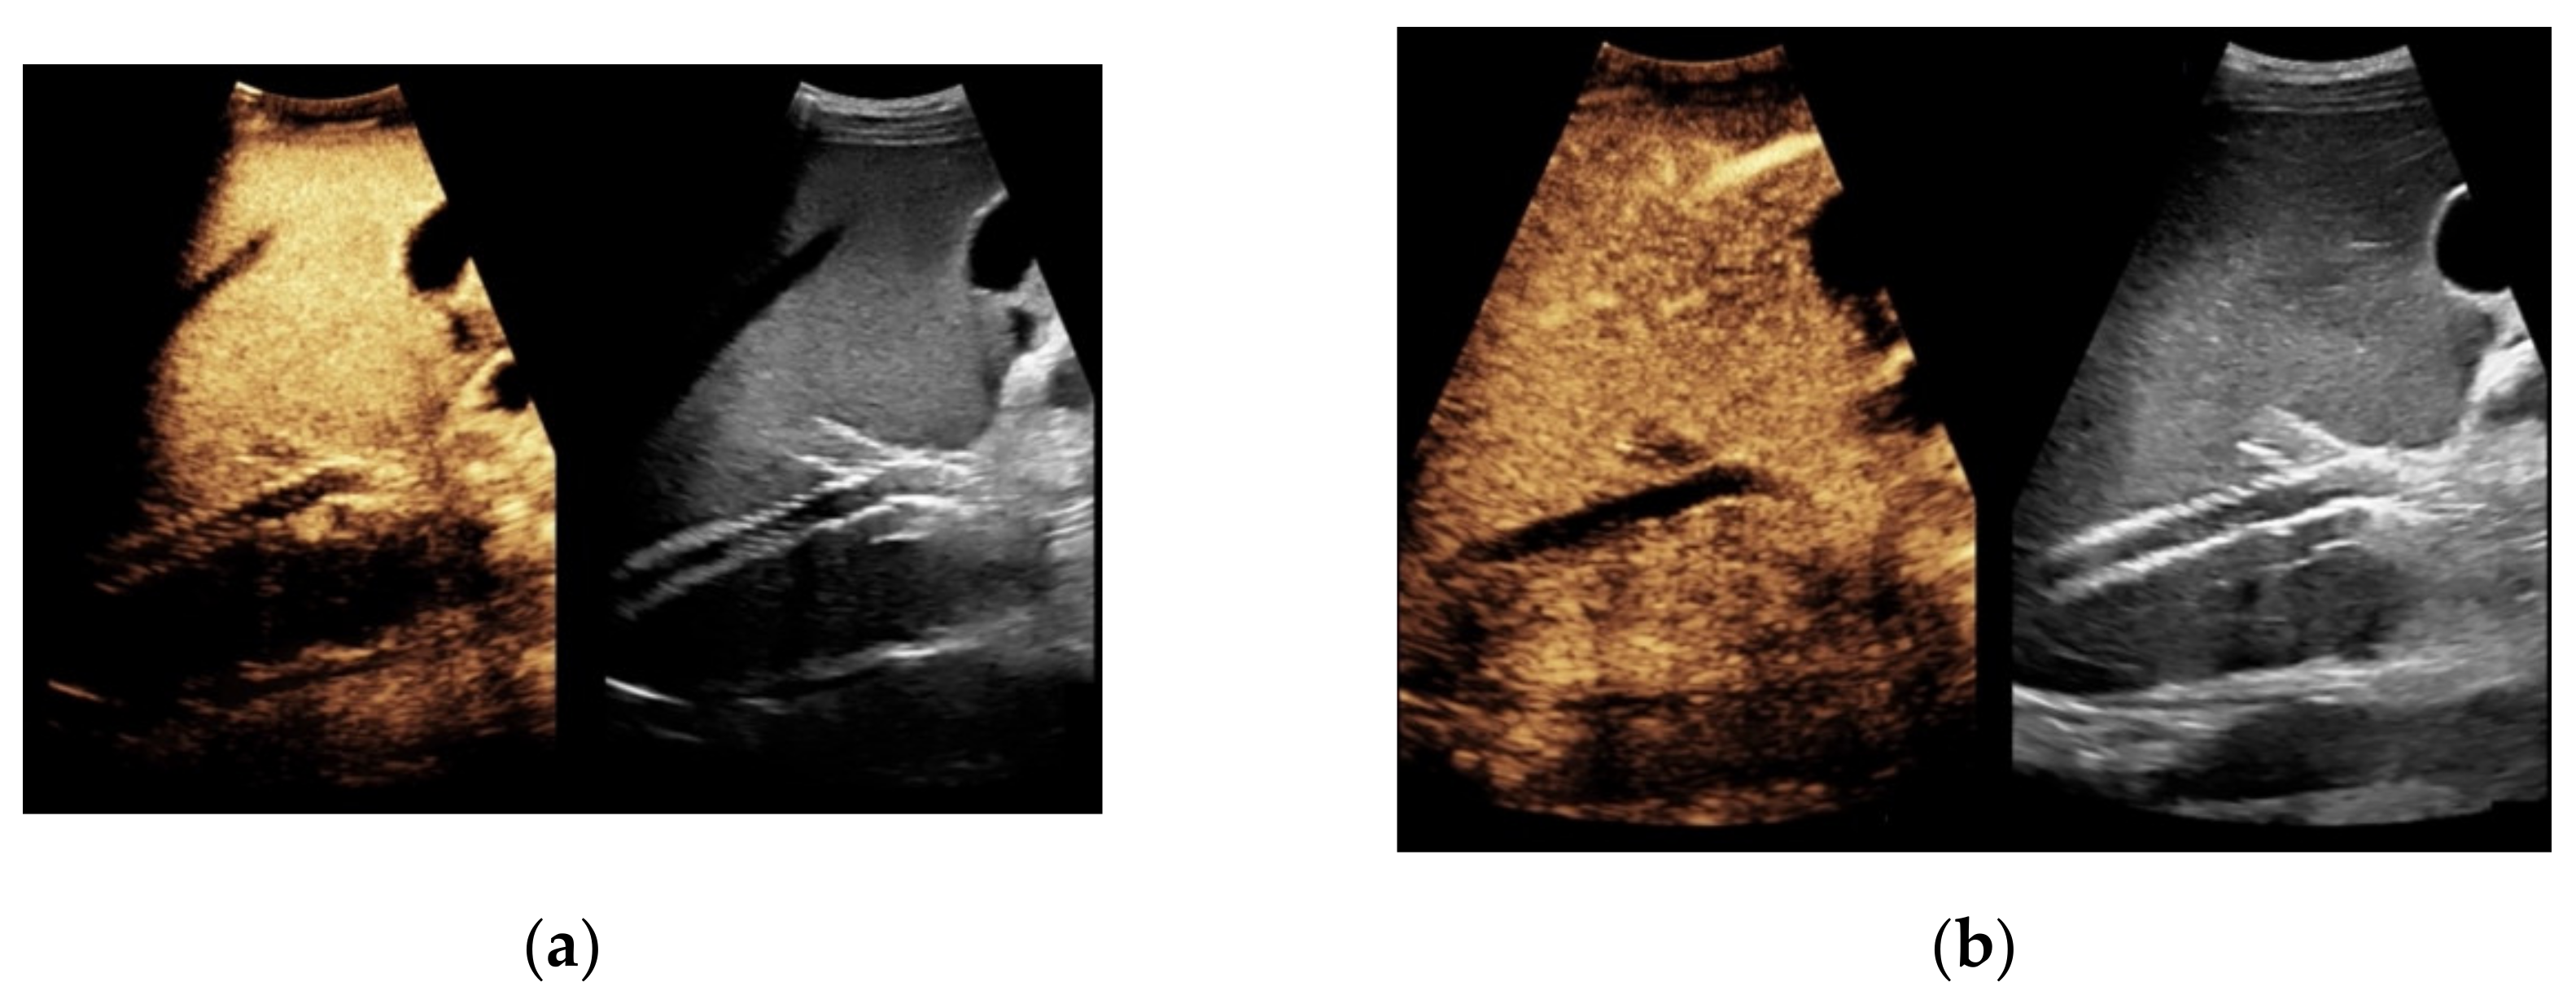

Figure 4. Same patient as in Figure 1 with continuous flow within the transjugular intrahepatic portosystemic shunt (TIPS) without thrombosis or occlusion using microflow imaging (a) and after administration of contrast agent (b,c).

When taking a closer look at the results of the CEUS examinations, 70.8% (n = 75) of the patients showed regular stent perfusion (Figure 4), 17.9% (n = 19) of the patients featured TIPS occlusion (Figure 5) while 6.6% (n = 7) patients had stent thrombosis (Figure 6). In contrast to the results from CDUS, there were no patients with only partial accessibility of the TIPS during CEUS, while the two patients with meteorism also were not assessable during CEUS. The three patients categorized in “others” showed simultaneous findings between CDUS and CEUS (Table 2).